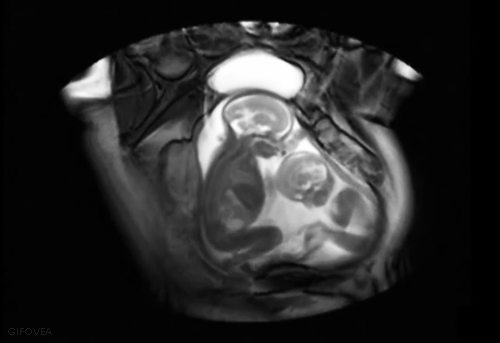

如果一次植入放2颗胚胎,可能会出现以下5种情况:

1)一次植入的两个胚胎,两个都存活下来了;

2)一次植入的两颗胚胎存活一个,流产掉一个;

3)两颗胚胎中,有一颗胚胎继续分化,形成了三胞胎;

4)两颗胚胎都继续分化,形成了四胞胎;

5)最不幸运的情况是,两颗胚胎都流产掉了。

1)单胎孕期为40周,也就是我们常说的怀胎十月;

2)双胎的孕周平均约为36周,比单胎妊娠减少4周,也就是减少1个月的时间;

3)平均的三胞胎孕周为32周;

4)平均的四胞胎孕周为28周。

所以,平均算下来,多移植一个胚胎,孕周减少1个月。现实中,实际孕周可能会有增减。